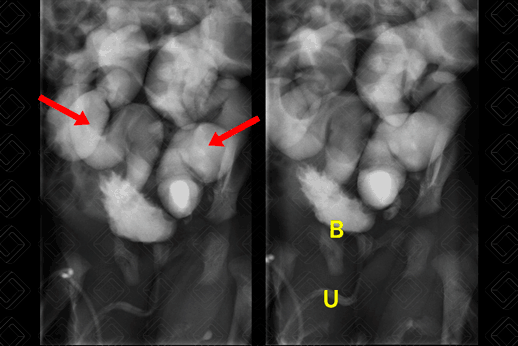

Texto alternativo para a imagem Figura 3. Créditos: Dra. Elazir Mota - Rio de Janeiro/RJ

Descrição da figura 3: Paciente com 5 dias de vida, investigando hidronefrose fetal. Bexiga pouco repleta, de paredes irregulares. Observa-se, ainda, refluxo vesicoureteral bilateral, com acentuada dilatação e tortuosidade dos ureteres (setas vermelhas), bem como distensão dos sistemas coletores intrarrenais – grau V. Legenda das siglas: B - bexiga; U - uretra (cheia durante a micção).